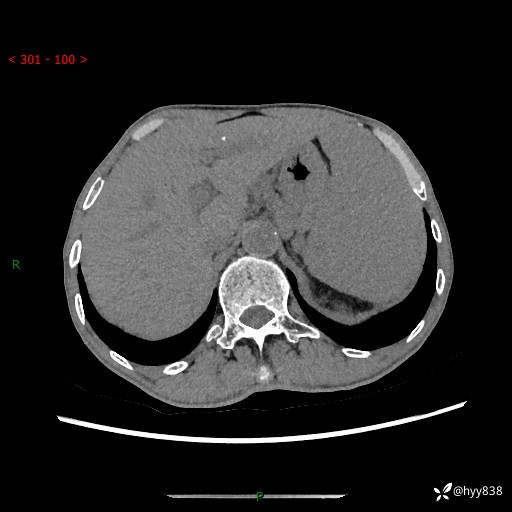

老年男性,脾大并脾脏弥漫粟粒状低密度,淋巴瘤 VS 肉芽肿 VS 血管瘤---结果公布

简要病史: 患者于3月前无明显诱因出现脾大,伴腹部轻微不适,具体不详,无腹痛、腹泻、腹胀,无头晕、头痛、乏力,无恶心、呕吐、呕血,无胸闷、气短、胸痛不适

上腹部CT平扫+增强